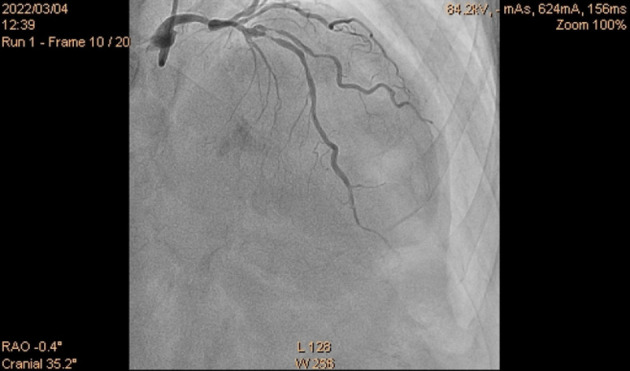

Planning and guiding PCI in a complex intervention is very important and one of the most important decisions is the one on whether to use one or two stent bifurcation techniques. Unfortunately, this can easily turn into complication and the need to alter the procedural strategy. The main points to be considered when deciding on the PCI strategy are related to both procedural safety and long-term outcomes. Provisional stenting has been recommended as the default technique for most coronary bifurcation lesions. In this paper, we describe the case of a patient scheduled for elective procedure of bifurcation lesion of LAD/D1. Our planned strategy was provisional stenting of LAD, using one stent for LAD, DCB for D1. Due to the complication that occurred, i.e., dissection of LAD after LAD stenting, we changed the strategy to two-stents technique strategy, using Culotte technique.

在复杂的介入治疗中规划和指导PCI是非常重要的,其中最重要的决定之一是是否使用一种或两种支架分叉技术。不幸的是,这很容易变得复杂,需要改变程序策略。在决定PCI策略时要考虑的要点与手术安全性和长期结果有关。临时支架置入术被推荐为大多数冠状动脉分叉病变的默认技术。在本文中,我们描述的情况下,病人计划择期手术的分叉病变的LAD/D1。我们计划的策略是LAD临时支架置入,LAD使用一个支架,D1使用DCB。由于LAD支架置入术后LAD发生夹层等并发症,我们将策略改为双支架技术策略,采用Culotte技术。